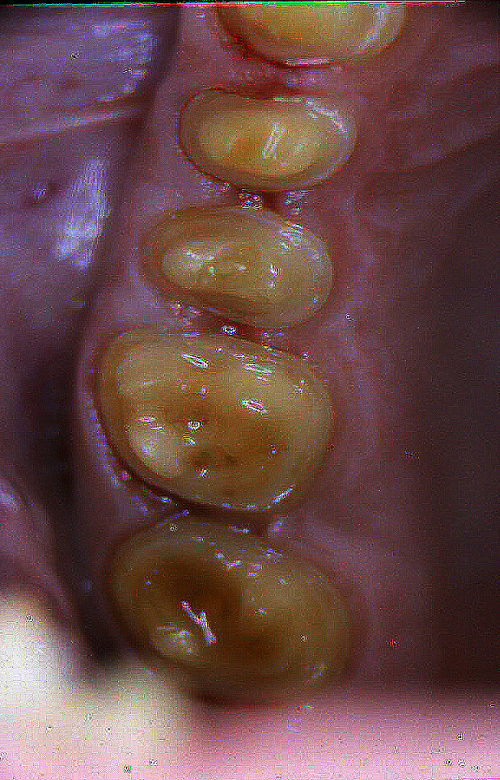

ABSTRACT El Bruxismo es una entidad patológica en la que concurren diferentes factores. Entre ellos el stress que conlleva consigo la vida moderna, constituye el Factor Predisponente sobre el que se ha abundado en innumerables tratamientos de tipo general, actuando sobre la psiquis y el comportamiento del individuo, ya sea con fármacos o bien mediante medios psicológicos. Sin embargo, como tantos desequilibrios provocados por el stress, confluyen siempre con un Factor Desencadenante, que en el caso del Bruxismo se encuentra en las desarmonías entre los componentes varios del Sistema Estomatognático. DESARROLLO Paciente varón, de 43 años, constitución atlética. A la inspección se observan desgastes oclusales que alcanzan la calidad de Facetas Parafuncionales, con dentina expuesta y empastes totalmente gastados y evidentes signos de falta de Disclusión Canina de ambos lados. Sobre dicho montaje se realiza un Encerado Progresivo de Diagnóstico, aportando en el mismo los elementos necesarios para obtener todos los principios básicos de una Oclusión Orgánica. FIG. 6 a 24 Una vez aprobado el fisiologismo de la oclusión en el articulador, se reproducen modelos de yeso con la nueva situación, y se estampa un SET UP en cada maxilar. FIG. 25/26 Procedemos entonces al tallado de las piezas correspondientes a la Guía Anterior, y rebasamos los estampados, creando en boca una nueva situación desoclusiva, que permanece en boca durante los pocos días que transcurren entre la primera y segunda visita de trabajo. FIG. 27/33 Ya abordando en esta segunda visita los sectores posteriores, tanto superiores como inferiores, tallamos siempre de manera supragingival, destacando la importancia vital de la forma obtenida en las provisionales, a las que abrimos plenamente las troneras para lograr una correcta higiene. FIG.34 a 43 FIG. 44 a 52 Efectuados los colados en oro y probados en boca, en el laboratorio se confecciona el bizcochado de la nueva Guía Anterior, la que puede o no copiarse de la Guía Anterior provisional, mediante la técnica denominada Trayectoria Funcionalmente Generada, que consiste en realizar en la platina del articulador un registro estereográfico sobre acrílico Duralay en polimerización. FIG. 57/58 Ajustados todos los detalles mediante esta técnica, se instala en boca en forma Provisional y se deja funcionando una semana o dos, al cabo de las cuales se chequean las disclusiones , los ajustes, la eficacia masticatoria, la carencia de sintomatología articular y muscular. FIG.59 a 63 PIE DE FOTO FIG.9 OBTENCIÓN DE LA GUÍA ANTERIOR FIG.10 Y 11 PITOMBOS. ALINEAC. TRIDIMENSIONAL FIG.12 PITOMBOS. DISCLUSIÓN DER. FIG.13 PITOMBOS. DISCLUSIÓN IZQ. FIG.14 WILSON INF. FIG.15 WILSON SUP. FIG.16 BOCA DE PEZ INF. FIG.17 BOCA DE PEZ SUP. FIG.18 VISTA OCLUSAL FIG.19 O.R.C. FIG.20 DISCLUSIÓN DERECHA FIG.21 CRESTAS TRIANG. INT. FIG.22 CRESTAS TRIANG. INT. FIG.23 CRESTAS TRIANG. INT. FIG 24 CRESTAS TRIANG. INT. FIG.59 DISCLUSIÓN IZQ. FIG.60 DISCLUSION IZQ. FIG.61 DISCLUSIÓN DER. FIG.62 DISCLUSION DER. FIG. 63 AJUSTE PERIFÉRICO

Con síntomas dolorosos y dinámicos en la ATM, con un estado periodontal sano y marcadas hipertrófias maseterinas.

Su condición de “borde a borde” también impide la disclusión en propulsiva, compartiendo en todas las excursiones las fuerzas con las piezas posteriores.

FIG.1 a 5